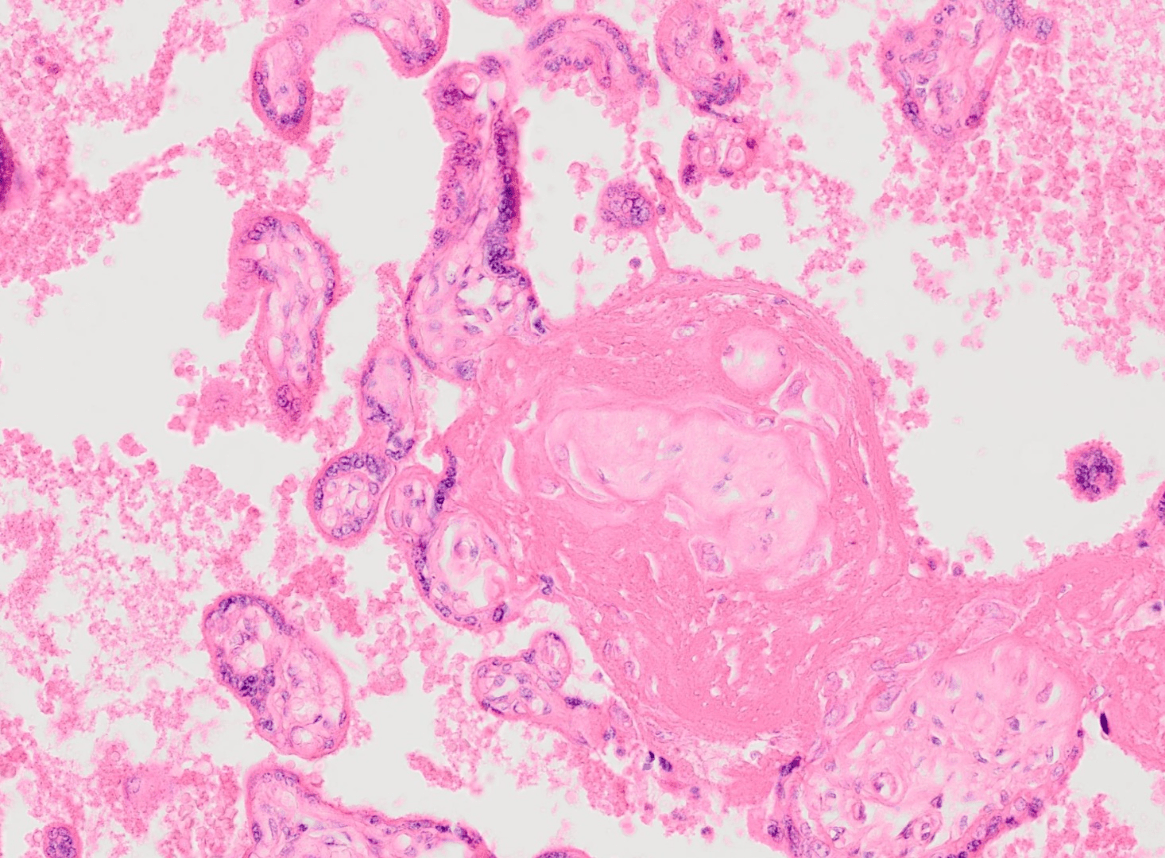

In diesem Organ sind Hofbauer-Zellen zu Hause.

Plazenta